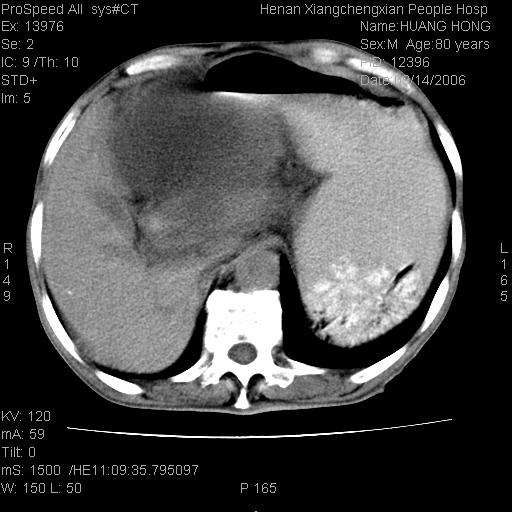

患者, 男, 80岁, 发现上腹部包块1年余,无其它不适.2006-9-14ct片是喝水后扫描2006-9-15ct片没喝水扫描![]() ![]() ![]() ![]() ![]() ![]() ![]() ![]() ![]() ![]() ![]() ![]() ![]() ![]() ![]() ![]() 以上是喝水片 以下是空腹片 ![]() ![]() ![]() ![]() ![]() ![]() ![]() ![]() ![]() ![]() ![]() ![]() ct:胰腺前方、肝脏与胃之间可见巨大类圆形囊性低密度影,大小约152mmx145mmx118mm,上缘平t11椎体上缘,下缘平l3椎体下缘,密度均匀,ct值15hu,其内呈多房分隔,囊壁薄且光滑,边界清晰,周围组织及器官明显受压。肝脏实质内未见异常密度影,胆囊未见异常,胰腺密度未见异常,脾脏大小、形态及密度未见异常,腹膜后间隙未见肿大淋巴结影。 印象:胰腺前方、肝脏与胃之间巨大类圆形囊性低密度影.性质待定。多考虑:.肠系膜巨大囊肿。 守望可可西里发言:支持楼主,考虑肠系膜囊肿,多为小肠系膜。 ysxyy发言:我总觉得这个病人虽然很像肠系膜囊肿,但还是应该强化一下; 下面这几幅图里肿块和主动脉的关系不太清,不知能否除外血管性来源? ![]() ![]() ![]() 病理结果:横结肠系膜间叶瘤.部分区域间质细胞增生活跃. 病理图片 ![]() 良性间叶瘤:是指由两种或两种以上的间叶组织所构成的混合性肿瘤.肿瘤仅发生在腹膜后和肠系膜,.前者较后者多发.良性间叶瘤常发生在肾或四肢,腹膜后较少见,各年龄均可发病.女多与男,预后较好,但术后易复法. 恶性间叶瘤:由两种以上恶性间叶组织成分组成. 光镜:肿瘤由脂肪/血管/平滑肌构成. 原贴地址: http://www.radinet.com.cn/forum_view.asp?forum_id=4&view_id=16217 ok |